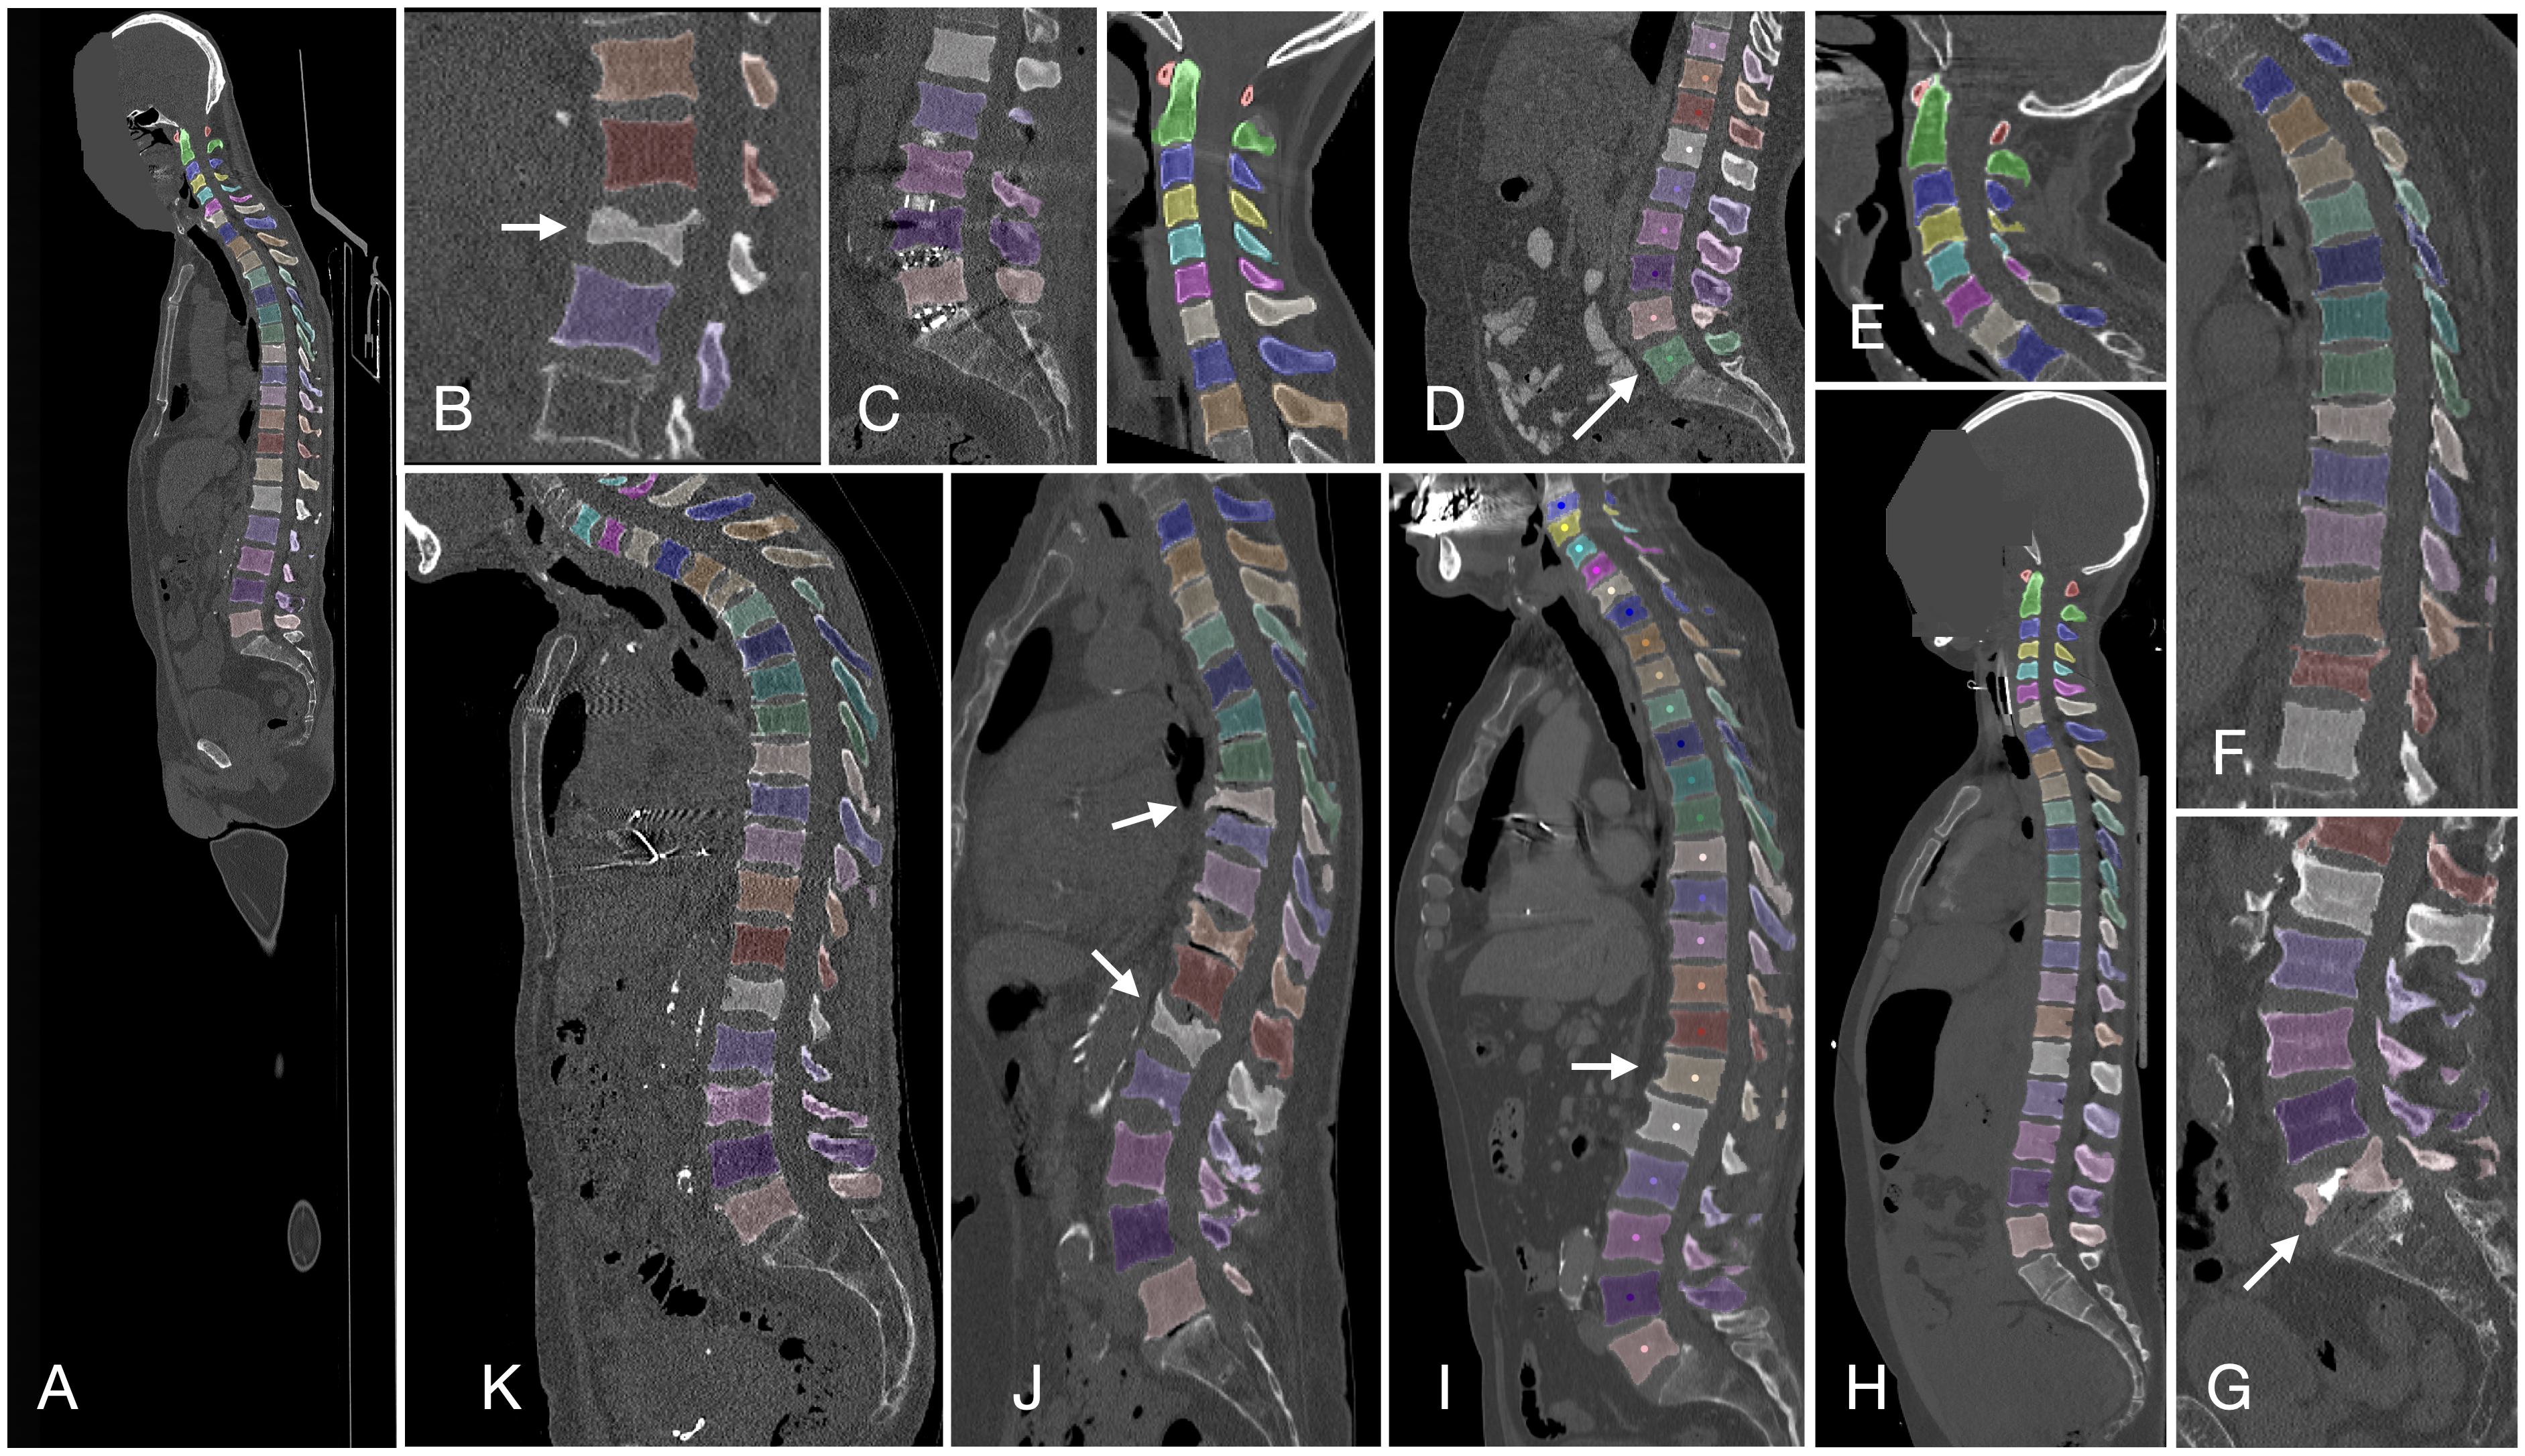

脊椎

Verse大规模脊椎分割数据集

| 名称 | 标注内容 | 类型 | 模态 | 数量 | 标签格式 | 文件格式 | License |

|---|---|---|---|---|---|---|---|

| VerSe | 脊椎 | 分割 | CC BY-SA 4.0 |